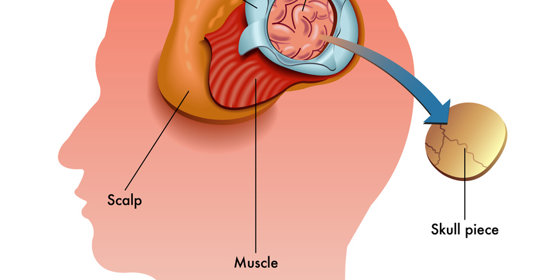

腦水腫:風險、治療與預防措施

腦水腫:處理方式與緊急性

本文介紹了開顱手術後腦水腫的原因及恢復注意事項。

腦水腫:症狀、後遺症、腦積水與手術治療